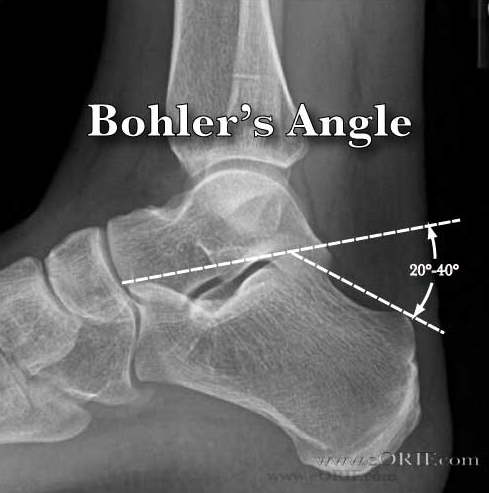

Describe and give normal values for Bohler’s angle

On a lateral view this angle is formed by the intersection of two lines.

First: line from the upper edge of the calcaneal body posteriorly to the upper edge of the posterior articular facet of the calcaneus at the subtalar joint.

A second line from posterior edge of articular facet to the upper edge of the anterior process of the calcaneus.

Normal is 20-40 degrees